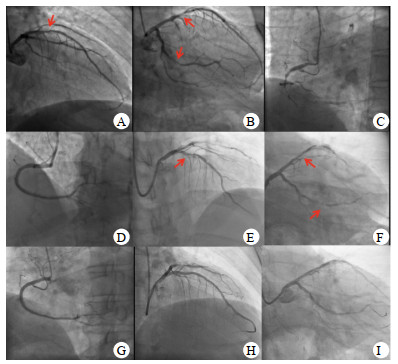

术后胸痛症状缓解,但喘憋,呼吸困难不能缓解。术后查体:脉搏90~100次/min,血压110~120/70 mmHg,呼吸频率30次/min,经皮指氧饱和度为80%。右肺呼吸音稍弱,未闻及干湿啰音,心界不大,心率90~100次/min,律齐,各瓣膜区未闻及杂音。腹软,无压痛,反跳痛,肝脾肋下未触及,肠鸣音5次/min。术后复查心电图:前壁导联ST段回落。心脏超声示:心脏各腔大小形态正常,射血分数(ejection fraction, EF)45%,后间隔中上段、下壁中上段及左室后壁心肌运动减低。右室游离壁运动减低,三尖瓣环收缩期位移10 mm,瓣膜未见功能异常。实验室检查:凝血项D-二聚体7 700 ng/mL(参考值0~243 ng/mL),N末端B型利钠肽原(NT-proBNP)2 248 ng/L(参考值0~125 ng/L),高敏肌钙蛋白T(hs-cTnT)0.027 μg/L(参考值< 0.017 μg/L)。血气分析提示:pH 7.40,二氧化碳分压35.7 mmHg,氧分压75 mmHg。立即完善肺动脉血管成像示:右肺动脉主干远端可见充盈缺损,右下肺动脉可见充盈缺损,左上肺动脉近端可见充盈缺损(图 3)。双下肢静脉、双侧髂静脉和下腔静脉血管超声均未见明显充盈缺损,血管通畅。双上肢动静脉和双侧锁骨下动静脉超声均未见充盈缺损,血管通畅。

| A纵切面可见右下肺动脉血栓,B横切面可见左肺动脉血栓;右肺动脉主干远端可见充盈缺损,右下肺动脉可见充盈缺损,左上肺动脉近端可见充盈缺损 图 3 患者肺动脉造影 |